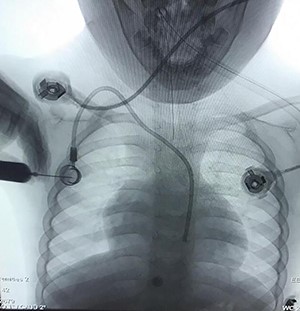

Case 2—a 60-year-old woman with breast cancer underwent a left mastectomy and an implantable chemotherapy port was inserted via right subclavian vein puncture, with fixation of the reservoir in the right thorax. She used her port for 12 months and was referred by an oncologist to explant the port catheter. The general surgeon missed the catheter when he wanted to separate the reservoir from the catheter, and vascular surgery consult was done. Chest radiograph was performed due to suspicion of catheter migration secondary to manipulated breakage of chemo port catheter. It showed that chemo port catheter had migrated from its original location to the right ventricle, traveling across the right atrium. The symptoms related to catheter migration that include palpitations, dyspnea, cough and chest discomfort were absent in this patient, and there was no electrocardiographic changes.

The right jugular vein was punctured, and a 6-Fr sheath was inserted. We removed the catheter from the right jugular vein. No major complication occurred during and after the procedure, and therefore, the patient was discharged on subsequent day (Fig. 3).